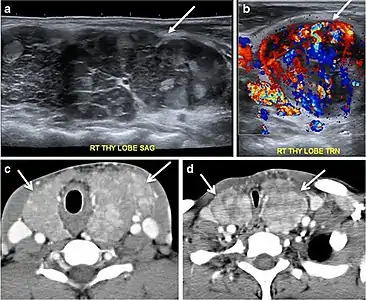

Fig. 3. An incidental PTC in a 62-year-old male patient with lymphoma. a, b Enhanced axial CT scan and fused PET/CT scan of the neck demonstrate a well-defined, hypodense right thyroid nodule (white arrow) with high FDG uptake. The FDG-avid uptake in the left side (circle) is related to patient's known lymphoma, which resolved after treatment. c, d Transverse greyscale and sagittal colour Doppler ultrasound of the neck demonstrate a right thyroid irregular hypoechoic lesion with some micro-calcifications (white arrows) and increased vascularity.[1]